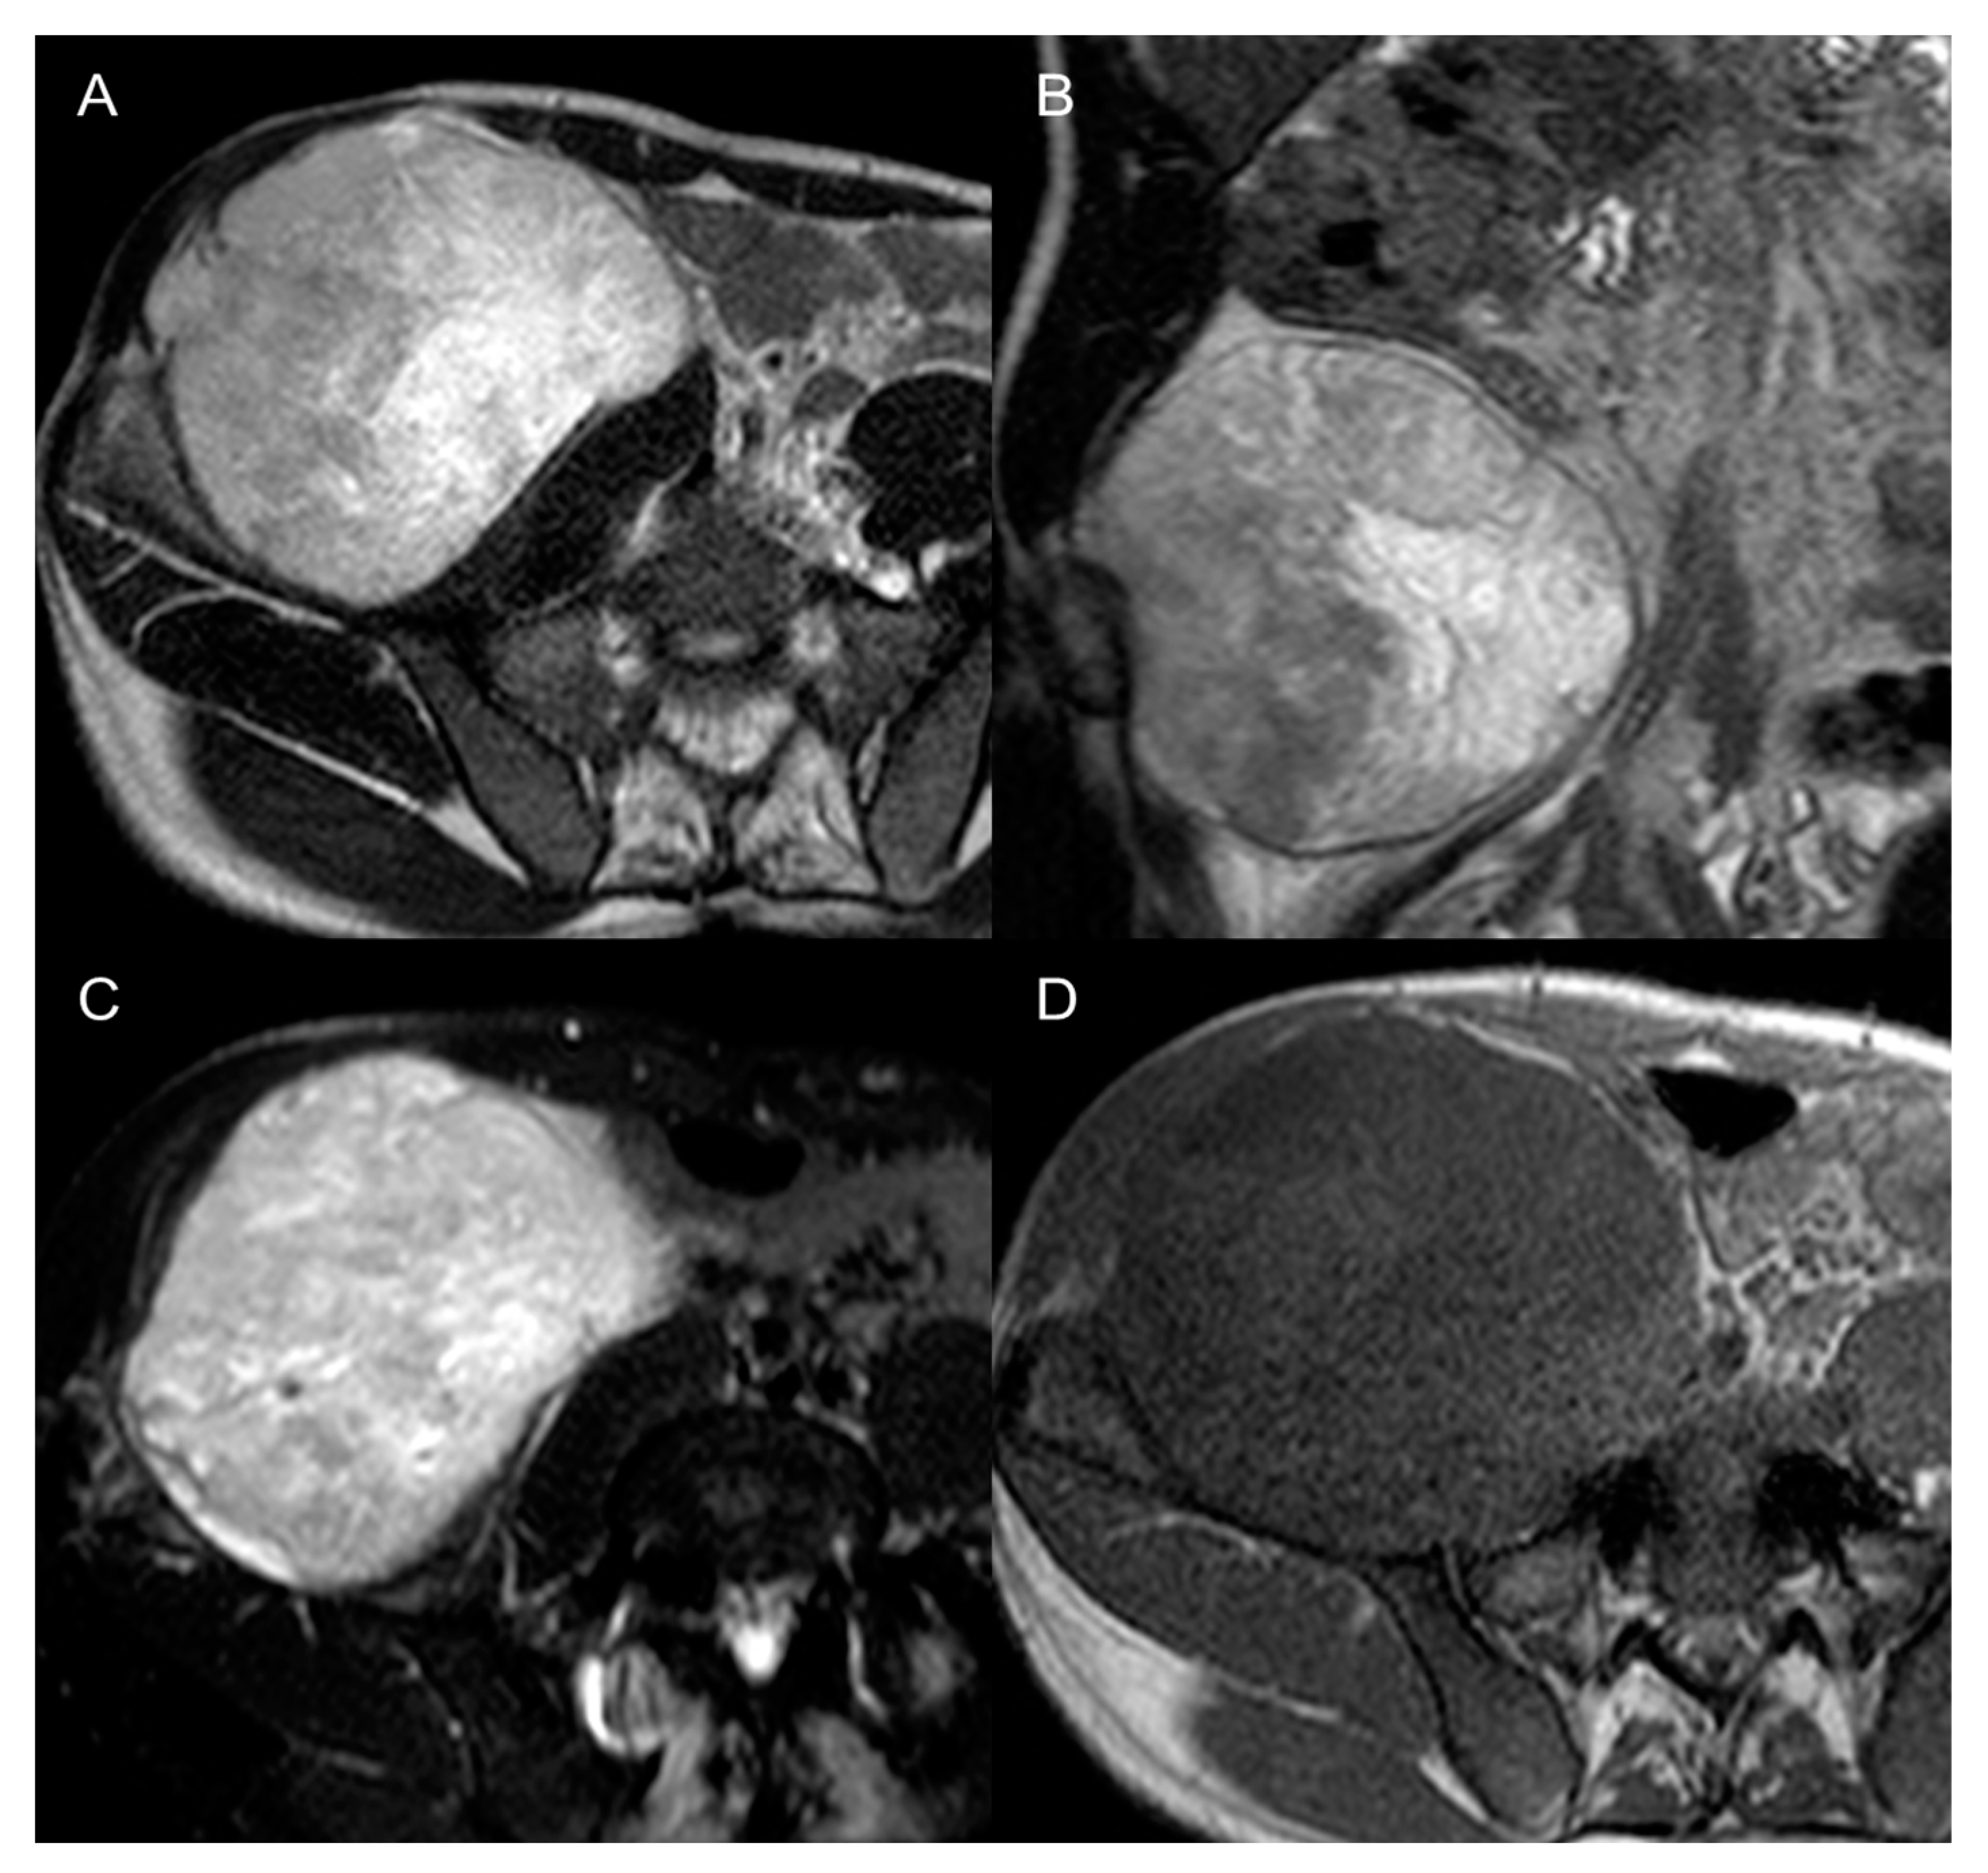

Contrast-enhanced MRI is the best modality to characterize a soft-tissue tumor, but also for local staging and prognosis. The diagnostic orientation can be facilitated on MRI by the identification of myxoid stroma (high fluid-like signal on T2, hypointense on T1, with contrast uptake), fatty content (Dixon [9] and Dual Echo), necrosis, hemorrhage, cystic degeneration, and fibrotic content. For instance, the presence of myxoid stroma can point towards myxoid round cells LPS, low-grade fibromyxoid chondrosarcoma, rhabdomyosarcoma (Figure 9), or small extraskeletal myxoid chondrosarcoma [9]. Undifferentiated sarcoma, instead, can present as massively hemorrhagic tumors, therefore being similar to a large hematoma, that does not have an explanation, nor a rapid appearance or resolution [6,9].

Figure 9.

Pleomorphic rhabdomyosarcomas in a 37-year-old man. Axial (A) and coronal (B) T2-weighted MR images, axial SPAIR (C), and axial T1 GRE (D) images show a 12 cm large heterogenous mass in the right retroperitoneum. The lesion was histologically confirmed at biopsy.

In myxofibrosarcoma and myxoid LPS, the water-like sign on T2-w sequences is related to high myxoid matrix content (≥75%) and has been associated with an increased risk of local recurrence and worse prognosis [48], as it is associated with shorter metastasis-free survival [27]. A higher amount (≥50%) of fatty content also seemed to correlate with higher grade and shorter metastasis-free survival [27] (Figure 10).

Figure 10.

Dedifferentiated retroperitoneal liposarcoma in a 50-year-old man. Axial (A) and coronal (B) T2-weighted MR images show an 8 cm fatty mass in the felt pelvis, with internal septa (arrows). The lesion was histologically confirmed after surgical excision.